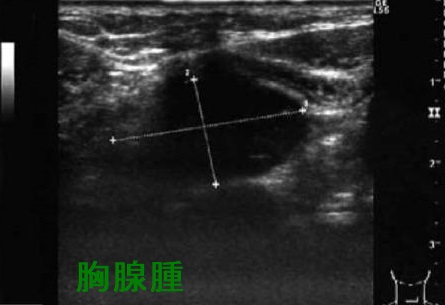

甲状腺超音波(エコー)上、胸腺腫は甲状腺の下に見え、内部不均一な腫瘤で、特徴的な所見に欠きます。小児の胸腺とは異なる見え方です。

心臓の上に乗っかるような形態なので、左に多く、CTで見ると、あたかも甲状腺結節・甲状腺腫瘤・甲状腺腫瘍のように見えます。